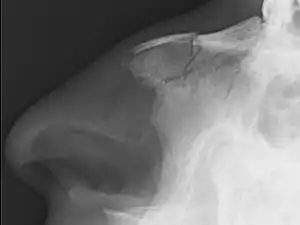

Nasal bone fracture

Bilateral nasal fracture as seen on CT scan